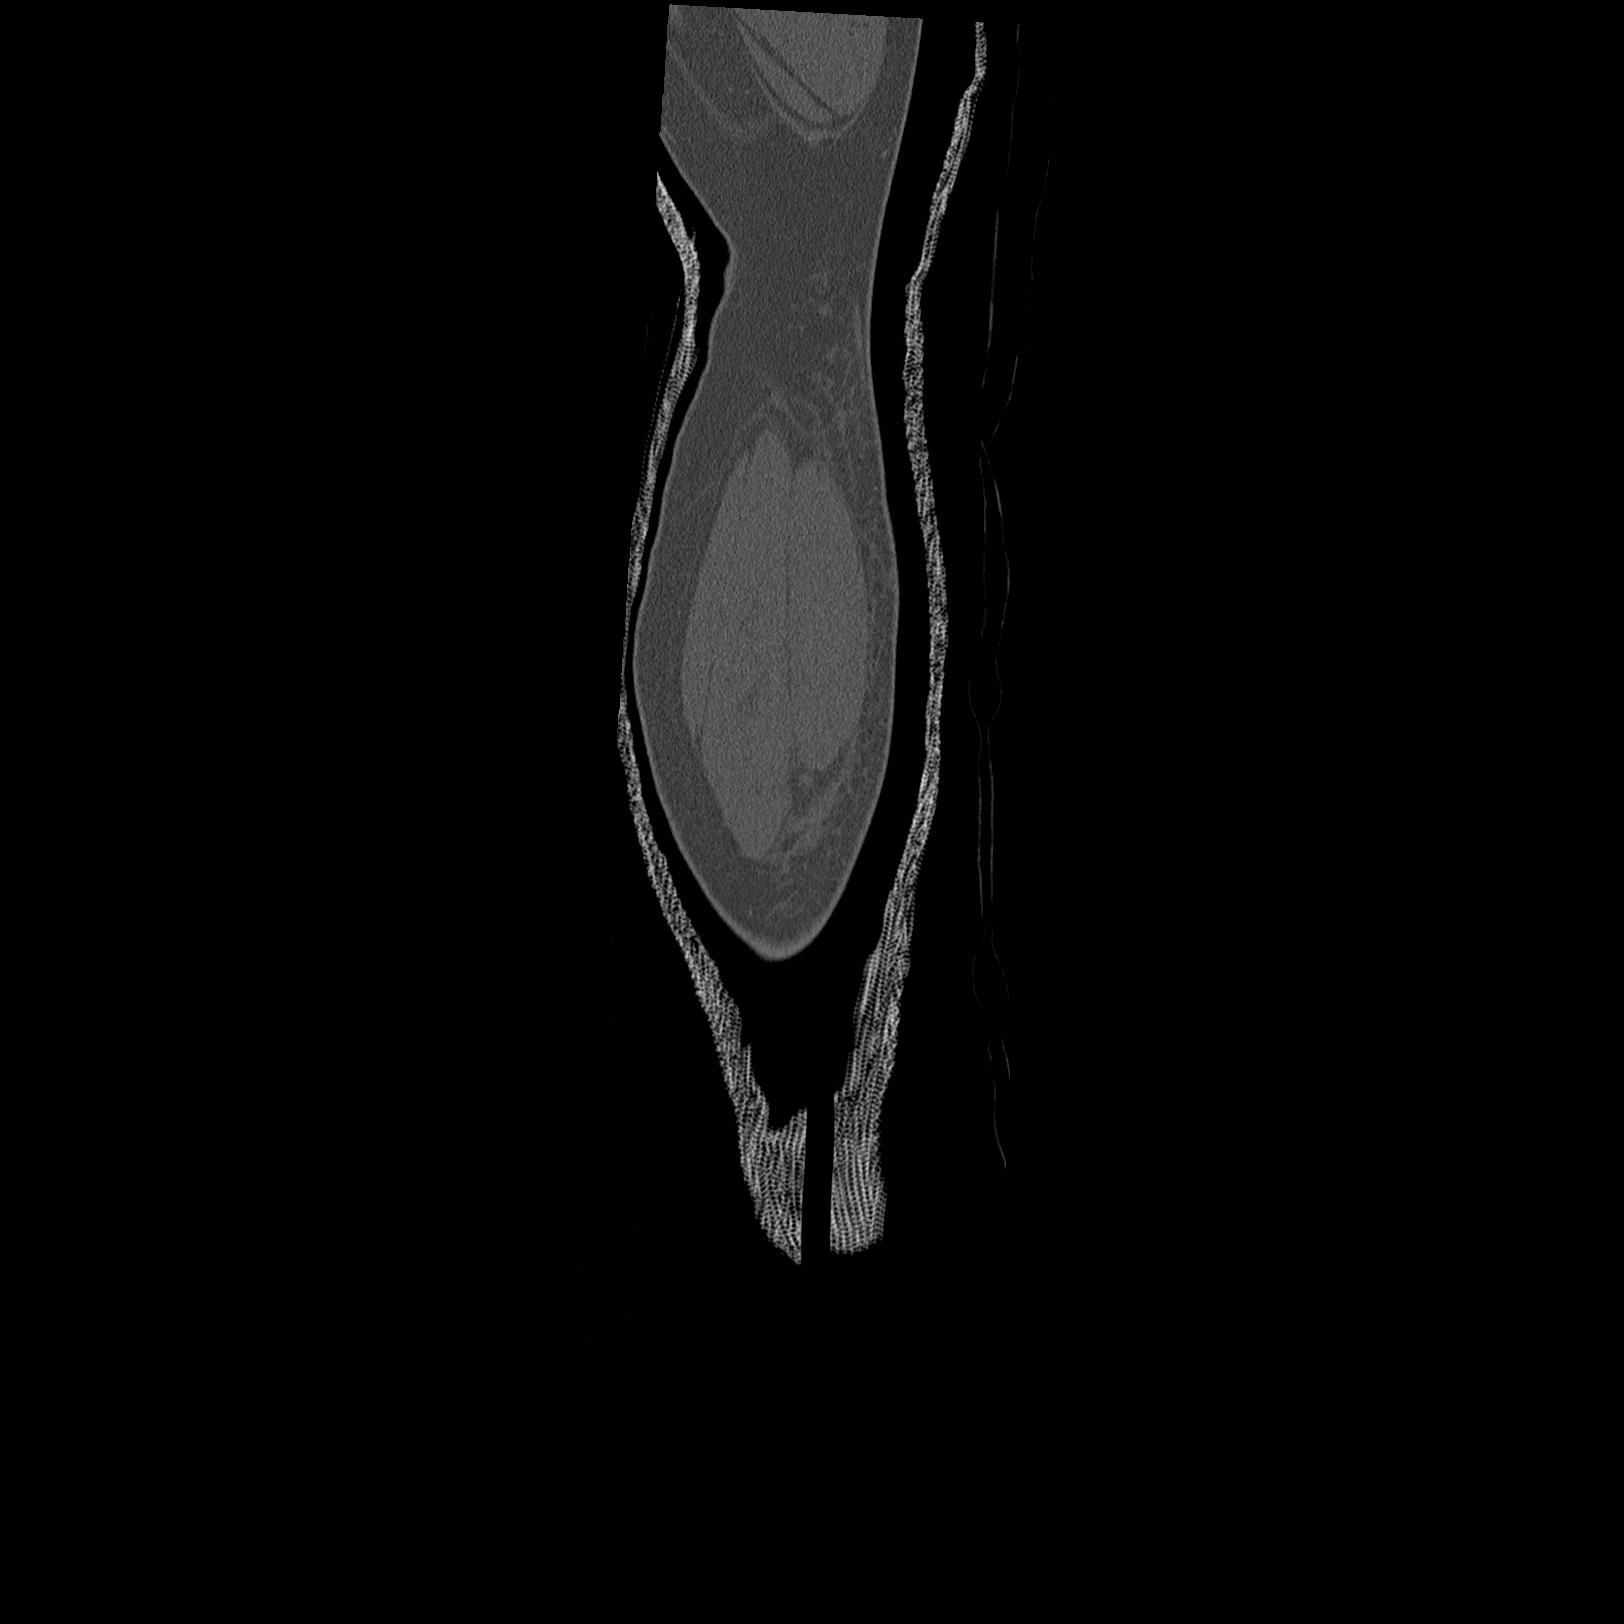

91983 11/16 左膝 2R 11/18 2R 55歳男性 脛骨骨切り術